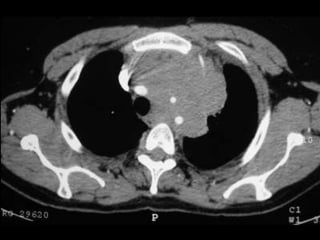

• Tomografía axial computada

TOMOGRAFIA

METODOS DIAGNOSTICOS • Radiografíade tórax • Tomografía axial computada • Resonancia magnética nuclear • Tomografía por emisión de positrones • Estudios de laboratorio • Estudios para la búsqueda del tumor primario • Estudios de estadificación